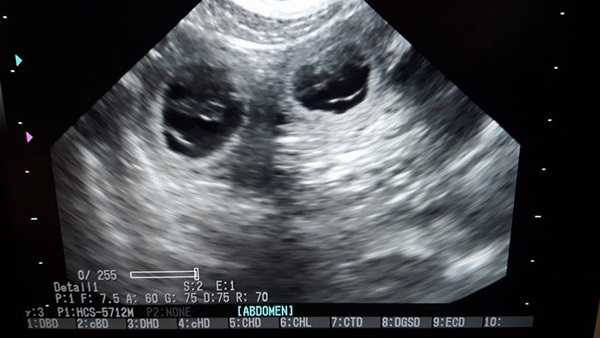

Heute morgen um 10 Uhr war Termin. Ich war sooooooooooooooo aufgeregt. Wir mussten erst noch etwas warten, weil wir natürlich viel zu früh da waren. Dann wurde der Bauch etwas rasiert und schon sprangen dem Ultraschallkopf die ersten 4 Fruchtanlagen entgegen. Da das kleine Schwarze nicht so lange still gehalten hat, können wir nur schätzen das es ein großer Wurf wird. Genaueres wissen wir dann bei der Geburt. Wir lassen uns überraschen und genießen jetzt die restliche Zeit.